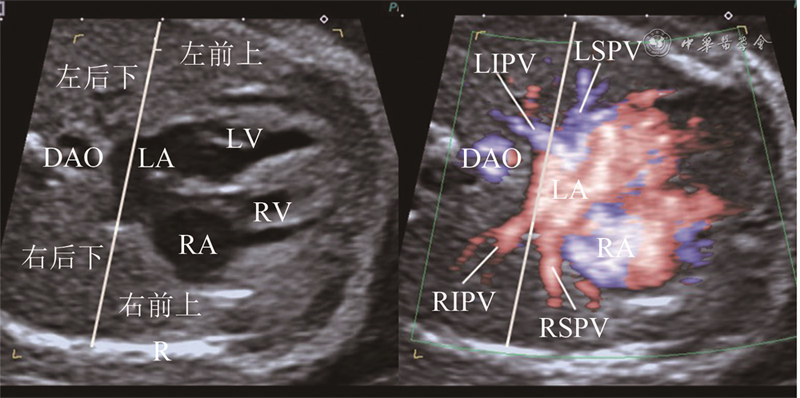

5例PAPVD胎儿部分区域肺静脉未回流入左心房,其中1例右上肺静脉直接回流入右心房,2例右上肺静脉回流入上腔静脉(图3),1例右上、右下肺静脉直接回流入右心房,1例左肺静脉变异为3支,最上支经无名静脉回流入上腔静脉。

图3 胎儿部分型肺静脉异位引流超声图像。左图为横向四腔心切面彩色血流显示左上肺静脉远端分支分布于左侧前部1/2肺野,左下肺静脉远端分支分布于左侧后部1/2肺野,右下肺静脉远端分支分布于右侧后部1/2肺野,3支肺静脉回流入左心房;右图为三血管切面彩色血流显示右上肺静脉远端分支分布于右侧上部肺野,近端未汇入左心房,汇入上腔静脉

应用区域血流追踪法沿肺静脉血回流4个区域追踪胎儿肺静脉分支能够提高PAPVD的检出率,本研究发现了5例PAPVD,这在以往很难诊断10。其中2例胎儿右上肺静脉回流入上腔静脉,这2例在检查过程中发现右侧前上部1/2肺野的肺静脉血没有回流入左心房,继续追踪其回流入上腔静脉。其中1例胎儿左心房可见4个肺静脉分支开口,但在区域血流追踪过程中,发现左肺上部肺野部分血流没有回流至左心房,而是经无名静脉回流入上腔静脉,即左肺静脉有3个分支,最上支异位引流。